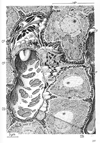

肝臓【かんぞう】 Organ located in the upper right side of the abdomen in the hypochondrium. Its inferior border runs from the upper left to the lower right through the epigastric region. In healthy subjects its border does not reach below the costal margin. It moves with respiration and is thus palpable.(肝臓は身体内の最大の腺であり多様な機能を営むが、それを①胆汁の生産と分泌(腸管内へ)を行う、②炭水化物、脂肪、蛋白の代謝活動、③胃腸管から血液中に進入した最近や異物を細くする、とう3点に要約することができる。(1)位置と形状:肝臓は右上腹部ある巨大な消化腺で、重さは男で1,400g、女で1,200gほどある。色は暗赤褐色で、これは充満する血液によるものである。肝臓の表面が平滑で光沢に富むのは腹膜(の臓側葉)におおわれているからである。肝臓の上面は横隔膜の下面に接して丸く膨らみ、横隔面と呼ばれる。横隔膜上の心臓に対応して、浅い心圧痕をみる。からだの正中にほぼ相当して、横隔面を大きい右半と小さい左半に二分する肝鎌状間膜が走る。これは肝臓の表面を被う腹膜が左右から翻転しながら寄り合い、その間に線維性の結合組織をいれるもので、肝臓を横隔膜から吊り下げる役をしている。このようにして横隔膜と肝臓は平滑な腹膜で自由に滑り動くようになっているが、後部のせまい領域では、両者が線維性結合組織によって密着して活動性に欠ける。肝臓表面のこの領域を無漿膜野(裸の領域Area nuda--腹膜に包まれていない--の意)という。無漿膜野は前方へ細く張り出して肝鎌状間膜につづき、左右へ細く伸びて左三角間膜と右三角間膜になる。左三角間膜の端は、肝臓の左上端を横隔膜につなぐ索をなして線維付属(Appendix fibrosa hepatis)とよばれる。肝臓の上面と下面の境界は前方でうすくするどい縁をなし、下縁(または前縁)とよばれる。上腹部を斜め右下方へ走る一線をなし、触診することができる。これと右肋骨弓の交点に胆嚢の底が腹壁直下に頭を出している。下縁の正中部には肝円索切痕とよぶ切れこみがあって、肝鎌状間膜をはさんでいる。肝臓の下面は上腹部の内臓に面するので、臓側面とよばれる。ここには矢状方向に走る2条のくぼみと、それを横に結ぶくぼみがHの字をなしている。Hの左縦線は前方の半分が肝円索をいえる肝円索裂、後方の半分が静脈管索をいれる静脈管索裂である。Hの右の縦線には前方に、胆嚢の上面をおさめる胆嚢窩があり、後方に大静脈をおさめる大静脈溝がある。H字の横線に当たる溝は肝門で、門脈、固有肝動脈、肝管のほか多数のリンパ管と若干の神経が通っている。肝鎌状間膜、肝円索裂、静脈管索裂によって、肝臓は大きい右葉と小さい左葉に分けられる。肝臓の臓側面では、右葉(広義)が胆嚢窩、大静脈溝、肝門によって狭義の右葉、中央前方の方形葉、中央後方の尾状葉に分けられる。尾状葉は全科法へ乳頭突起を出し、前右方へ、肝門の後縁に沿って尾状突起を出す。乳頭突起に対峙して左葉から小綱隆起が張り出し、両者の間に小綱をはさむ。(2)肝臓の構築:肝臓の表面は大部分腹膜をかぶり、その下に線維性の結合組織がある。この結合組織は大血管とともに肝臓内に侵入し、血管周囲線維鞘をつくる。ギリソン鞘(Glisson's sheath)ともよばれる。肝臓の実質は径1mm前後の短六(ないし五)角柱の肝小葉を構造単位として成り立っているが、肝門からはいる肝固有動脈と門脈の枝はグリソン鞘を伴って、この肝小葉の稜線(三つの肝小葉の合するところ)に沿って走るこの動静脈を小葉間動・静脈とよぶ。肝小葉の角柱の中心を貫いて中心静脈という太い毛細血管が走り、その周囲に肝細胞の板が放射状に配列する。肝細胞板(hepatic cell plates)は分岐し、吻合し、あなをもち、すきまに洞様毛細血管(sinusoidal capillaries)をいれている。小葉間動静脈の枝は小葉の洞様毛細血管に注ぎ、中心静脈から、小葉下静脈(Vena sublobularis)とよばれる小静脈を経て下大静脈へと流れていく。肝細胞板の中に、肝細胞のあいだを縫って走る細管系が毛細胆管(bile capillary)であって、肝細胞の産生する胆汁を運ぶものである。毛細胆管は肝小葉のへりで小葉間胆管とよばれる小導管に注ぎ、グリソン鞘の中を合流しつつ肝門へ向かう。(3)肝臓と血管:肝臓は門脈の番人というべき器官である。すなわち消化管から送られてくる血液中に余分の糖分があればグリコゲンとして貯え、有害物質があれば分解、解毒する。脾臓から送られる破壊血液のヘモグロビンをビリルビンに変えて胆汁中に排泄する。門間区によって運ばれてくる膵臓のホルモンは、肝細胞でのグリコゲンの産生とブドウ糖への分解を調節する。しかし、門脈血は酸素に乏しい静脈血であるから、肝臓は動脈血を固有動脈にあおがねばならない。胎生期においては、臍から前腹壁を上行して肝臓の下面に達する臍静脈(Vena umbilicalis)が、肝門で門脈と合して、そのまま肝臓の下面を後方へ走り、下大静脈に注ぐ。細静脈と下大静脈のこの短絡路を静脈管またはアランチウス(Arantius)の管と称する。生後、胎生期の循環路は閉鎖し、結合組織索として残る。臍静脈の遺残が肝円索、静脈管の遺残が静脈管索である。 (解剖学事典 朝倉書店より引用) 肝臓の生理 肝臓は重要な機能を営む器官であり、肝臓を楔状すると12時間前後で低血糖で死亡するといわれている(動物実験では70%の肝切除でも数週で機能が正常になるといわれている)。)